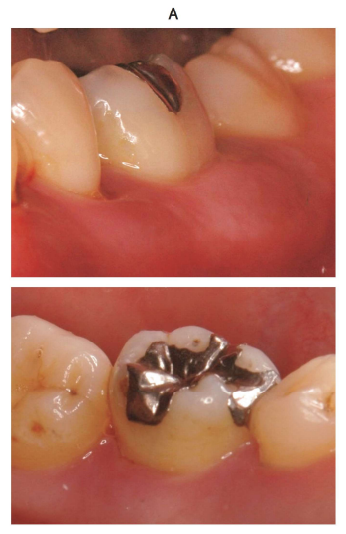

下顎左側第一大臼歯の口腔内写真(別冊No. 8A)とエックス線画像(別冊No. 8B)を別に示す。

治療方針で適切なのはどれか。 2 つ選べ。

解答:b c

解説:

X線画像より、根分岐部にプローブが完全に通りそうである。⇒3度の根分岐病変

a GTR 法:2度

b 歯根分離:3度

c トンネリング:3度

d FGF-2 製剤の応用:2度

e ファーケーションプラスティ:1,2度